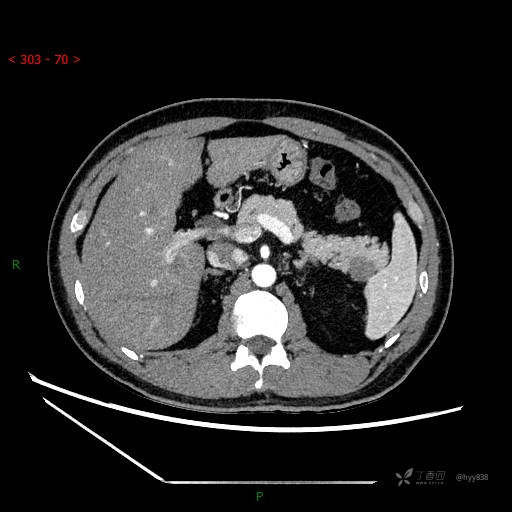

MRI(T1WI+T2WI-fs+DWI+ADC)